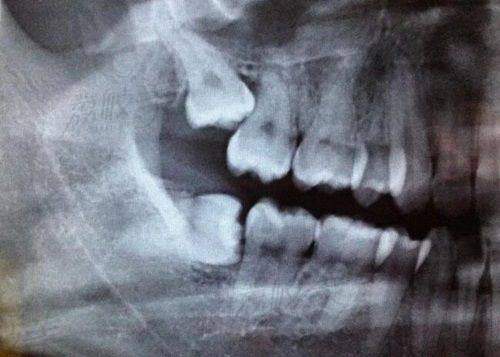

牙齿拍片200 - 300元需要了解牙齿内部情况者辅助医生诊断

口腔扫描检查120元起需要详细口腔数据者精细获取口腔信息